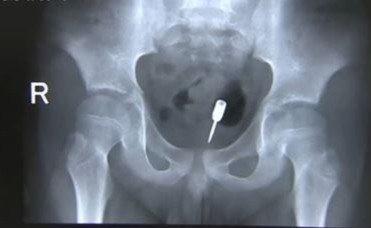

Người đàn ông nhập viện vì 'cậu nhỏ' gặp tai nạn hy hữu

Người đàn ông 33 tuổi nhập viện trong tình trạng dương vật bị sưng, phần gốc có vòng đai ốc có kích thước 2 cm.